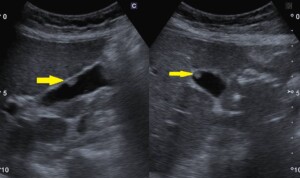

@腹部エコーで発見された胆のうポリープ